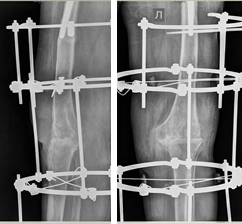

Остеосинтез коленного сустава

Остеосинтез коленного сустава 103 фотографий